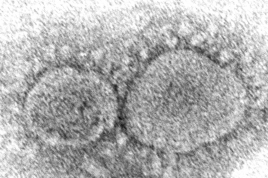

New coronavirus variants reported in L.A. and elsewhere raise worry about reinfections

Evidence is mounting that having COVID-19 may not protect against getting infected again with some of the new variants. People also can get second infections with earlier versions of the coronavirus if they mounted a weak defense the first time, new research suggests.

How long immunity lasts from natural infection is one of the big questions in the pandemic. Scientists still think reinfections are fairly rare and usually less serious than initial ones, but recent developments around the world have raised concerns.